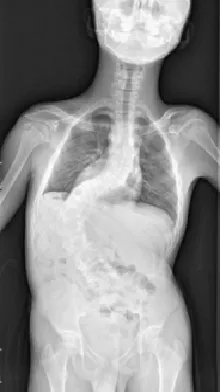

▷先天性脊柱畸形

先天性脊柱畸形,是指脊椎胚胎发育过程中,脊柱形成障碍或分节障碍所致的先天性脊柱畸形,包括侧凸、后凸和前凸,通常在婴幼儿期被发现。其中,半椎体畸形,尤其是完全分节的额半椎体,导致的脊柱侧凸保守治疗效果较差,早期诊断和手术治疗可避免严重的继发畸形,减少融合固定节段,保留更多的脊柱活动度,提高患儿生活质量。

▲ 女,3岁4个月,先天性脊柱侧弯半椎体畸形